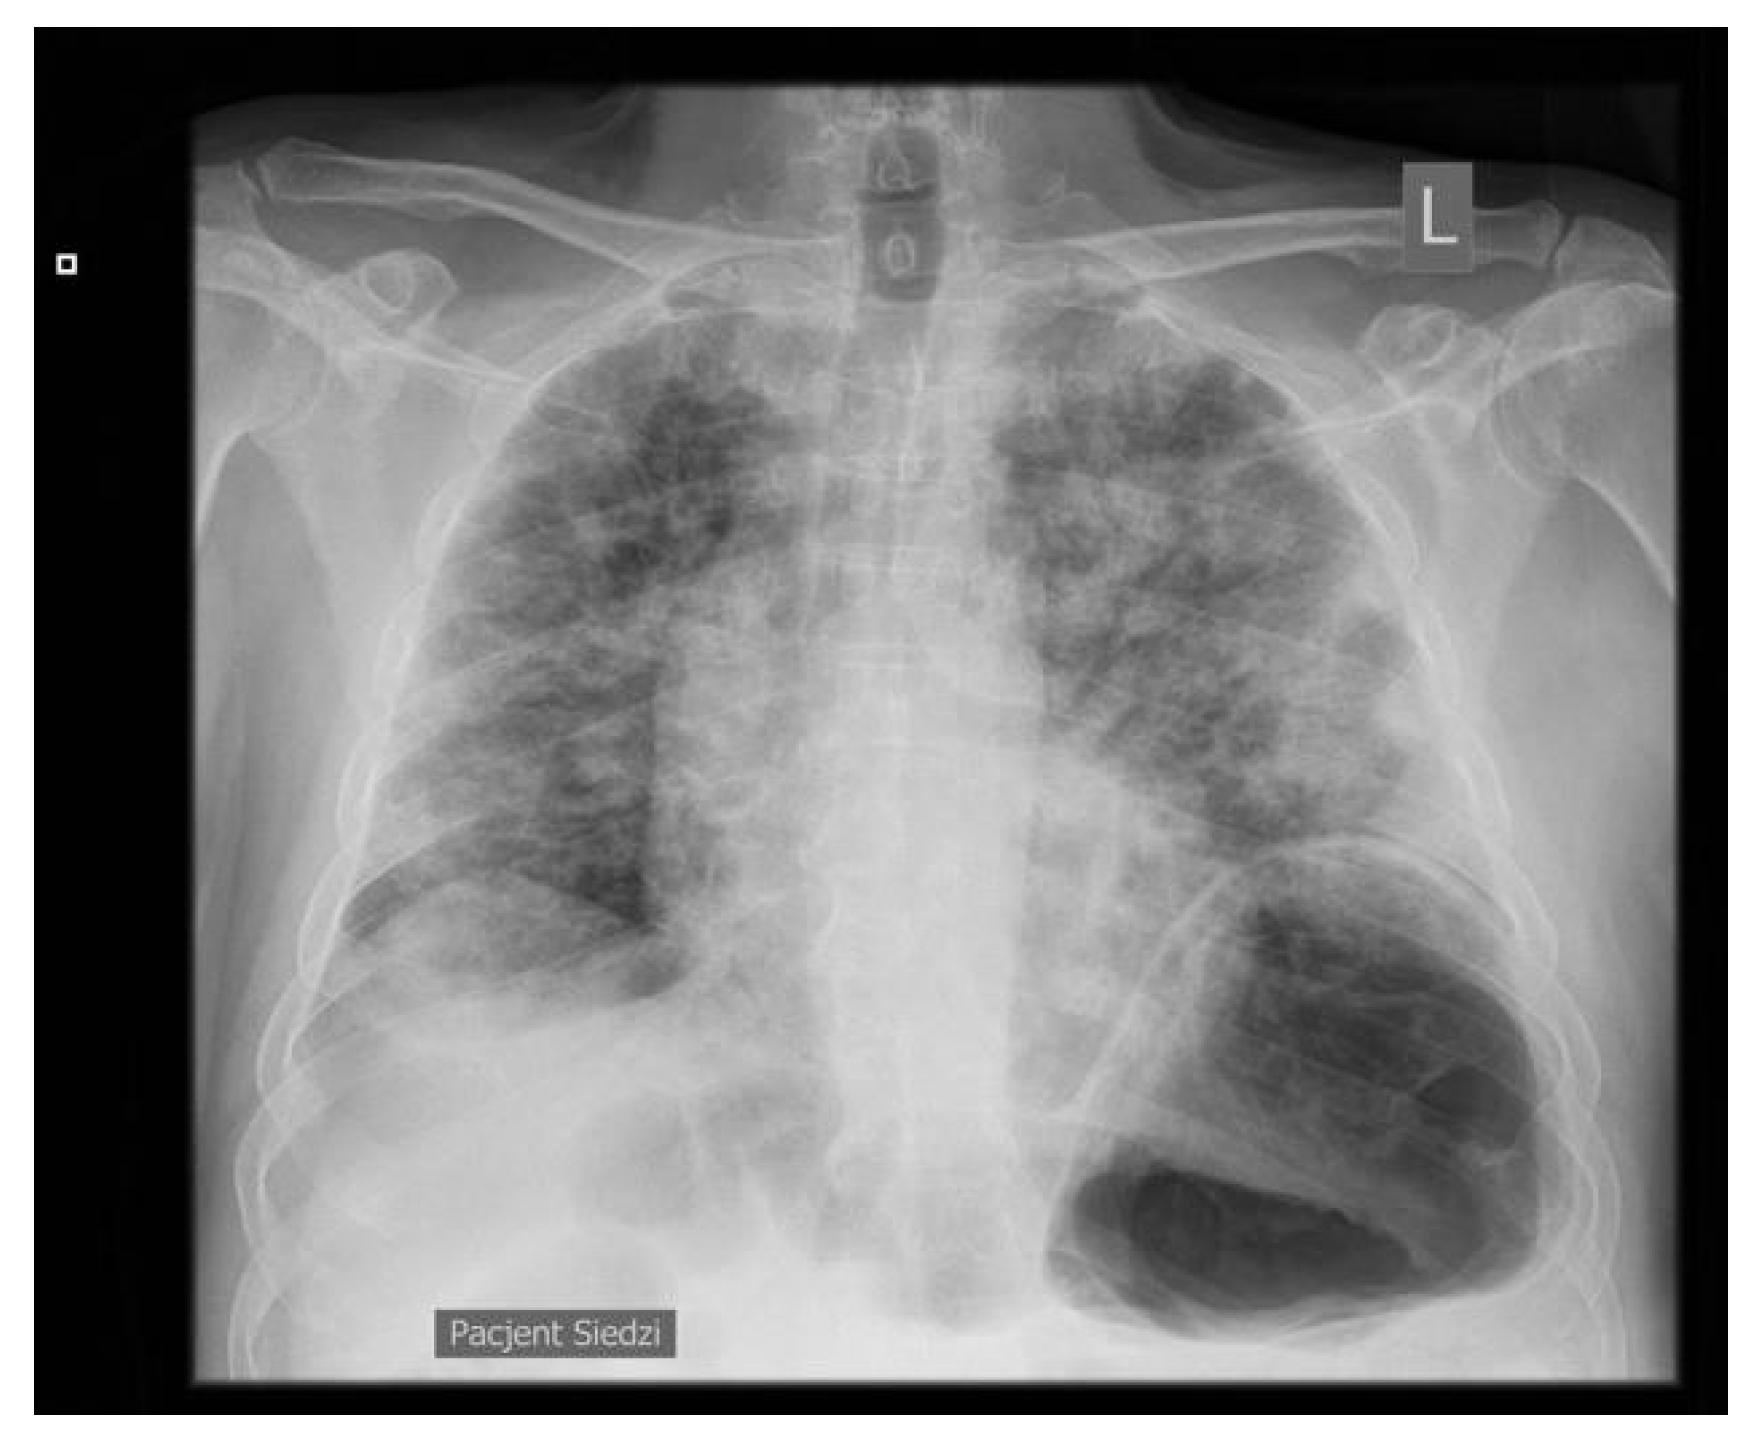

On day 3, the patient developed dyspnea, with bilateral rales and crackles over the lungs. On the chest X-ray, numerous signs of bilateral heterogenous shading with unclear etiology were observed (Figure 1).

Figure 1.

Chest X-ray. L—left side.